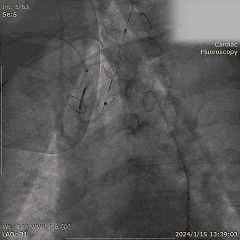

Step 6. 复查造影示瓣膜支架膨胀良好,少量瓣周漏

Step 7. Proglide闭合主入路股动脉,造影确认未见明显狭窄、渗漏